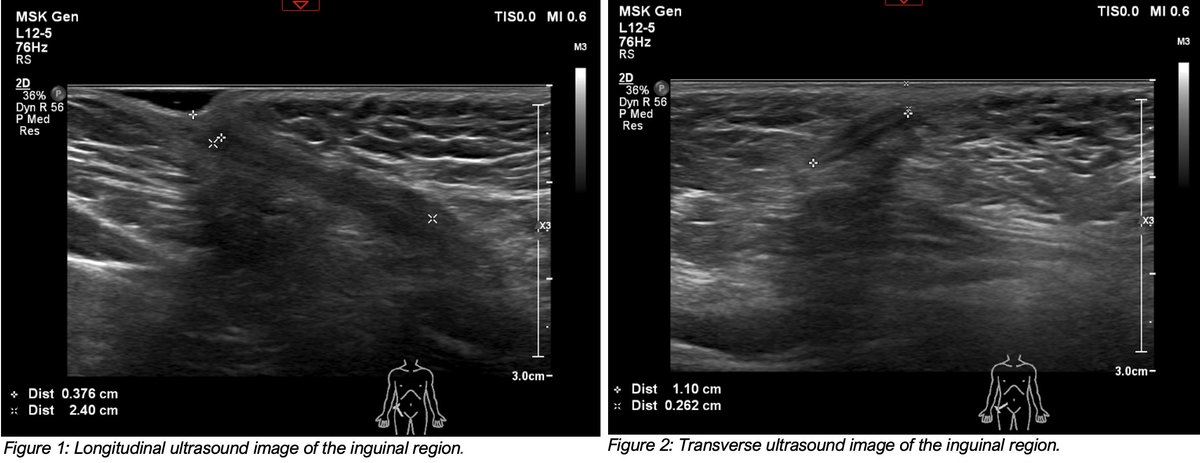

CASE: 3 y/o boy treated in ER for an incisional wound to medial right thigh, following injury involving broken glass. Patient presents again 9 months later, due to continued right groin pain & indentation of inguinal skin. What are the #ultrasound findings? https://t.co/ut1Rq537wv